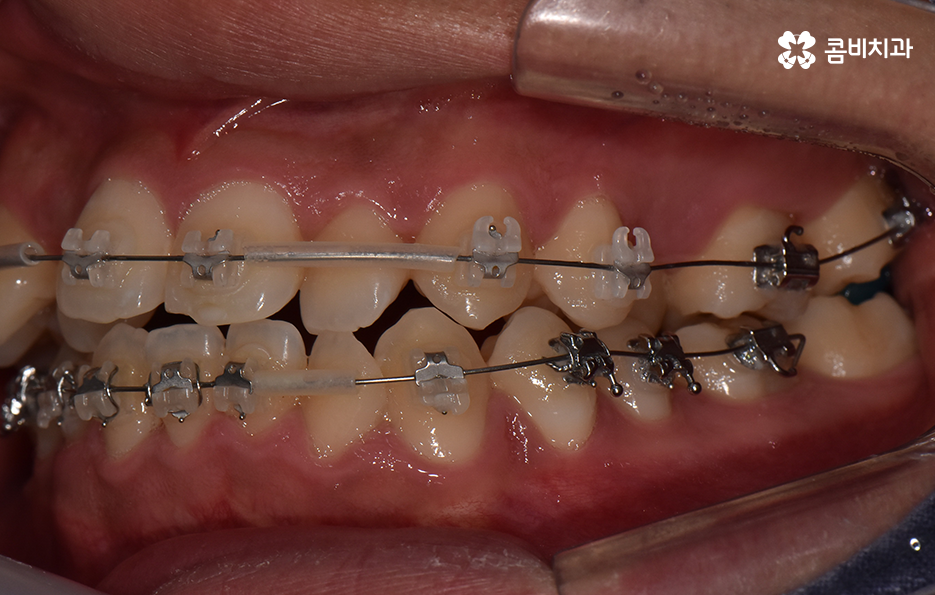

오늘 포스팅에서 보여지는 사진에서는 비발치 교정으로 덧니 교정이 가능했던 사례입니다. 덧니 교정 사례에서 발치교정 케이스는 흔한 치료 방법이긴 하지만 발치에 대한 판단은 치열만이 아니라 골격과 얼굴형을 종합적으로 고려하여 판단하고 치아를 얼마나 이동시켜야 할지 예측하여 판단하기 때문에 3D CT 등의 첨단 장비를 통한 검진과 경험 많은 교정 전문의와 충분히 상의하고 결정해야 합니다

종합하면 발치교정의 필요성은 얼굴과의 조화, 골격 그리고 교합 등을 전체적으로 고려하여 판단하기 때문에 각 환자분들이 필요한 치아의 이동 정도를 정확히 예측하고 필요한 치아 이동 공간을 확보함에 있어서 발치교정이 적합할지 아니면 비발치적인 방법으로도 치아 이동 공간이 확보 가능한지 따져보고 있으며 발치교정이 아니더라도 치간삭제, 악궁확장, 어금니 후방이동과 같은 방법으로 공간 확보가 가능하기 때문에 각 환자분들에게 적합한 1:1 맞춤형 치료가 진행되고 있어요